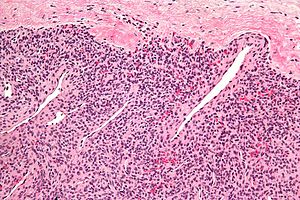

| LM | fascicular pattern (may be subtle) with compressed blood vessels (often thin walled & branching), increased peri-vascular cellularity; high cellularity; small bland unequally spaced epithelioid/spindle cells with moderate eosinophilic cytoplasm |

- Fascicular pattern - may be subtle - with:

- Compressed blood vessels, often thin walled & branching.

- Increased peri-vascular cellularity.

- Cellular lesion:

- Small bland unequally spaced epithelioid/spindle cells.

- Moderate eosinophilic cytoplasm.